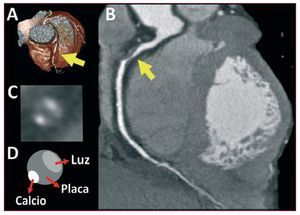

Existe un amplio consenso en que la cardio-TC es una técnica robusta para la detección y la cuantificación de enfermedad coronaria. Más importante es comprobar que se puede valorar la anatomía de la placa y encontrar datos asociados a vulnerabilidad77 o rotura78 (fig. 4).

Figura 4. Tomografía computarizada cardiaca en la valoración de la enfermedad coronaria. El estudio de un paciente con dolor torácico atípico demuestra la presencia de una estenosis severa en la coronaria derecha proximal. A: reconstrucción volumétrica. B: reconstrucción multiplanar de la arteria. C y D: la sección transversal del vaso a nivel de la lesión demuestra que el componente más voluminoso es placa no calcificada. El estudio aporta información diagnóstica y pronóstica indudable.

Uno de los campos actuales en la investigación con cardio-TC es la posibilidad de evaluar la repercusión funcional de las lesiones. Una posibilidad es demostrar una reducción de la opacificación coronaria distal a la lesión79. Sin embargo, el interés está centrado en los protocolos de estrés con adenosina o dipiridamol, que prometen obtener la misma información que la tomografía por emisión monofotónica (SPECT), con una dosis de radiación razonable80. Un abordaje alternativo serían los estudios híbridos que combinan la información anatómica de la TC con datos funcionales de la SPECT o la tomografía de emisión de positrones81.